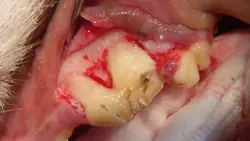

Step 5

Using a crosscut fissure bur (#701L, friction grip) and starting in the furcation area, the distal root is sectioned away from the mesial roots using light sweeping cuts until completely through the tooth (A).

Additionally, the distal aspect of this crown/root segment can be trimmed away with the bur to create space for the distal root to move caudally and for a dental elevator to be inserted (B). (Use caution not to cut or damage the maxillary 1st molar.) Otherwise this tooth root segment may be in a stalemate position-unable to move distally and too tight interproximally to adequately allow placement of a dental elevator.

A